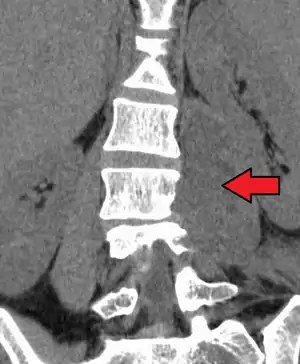

Paraspinal abscess in the psoas muscle